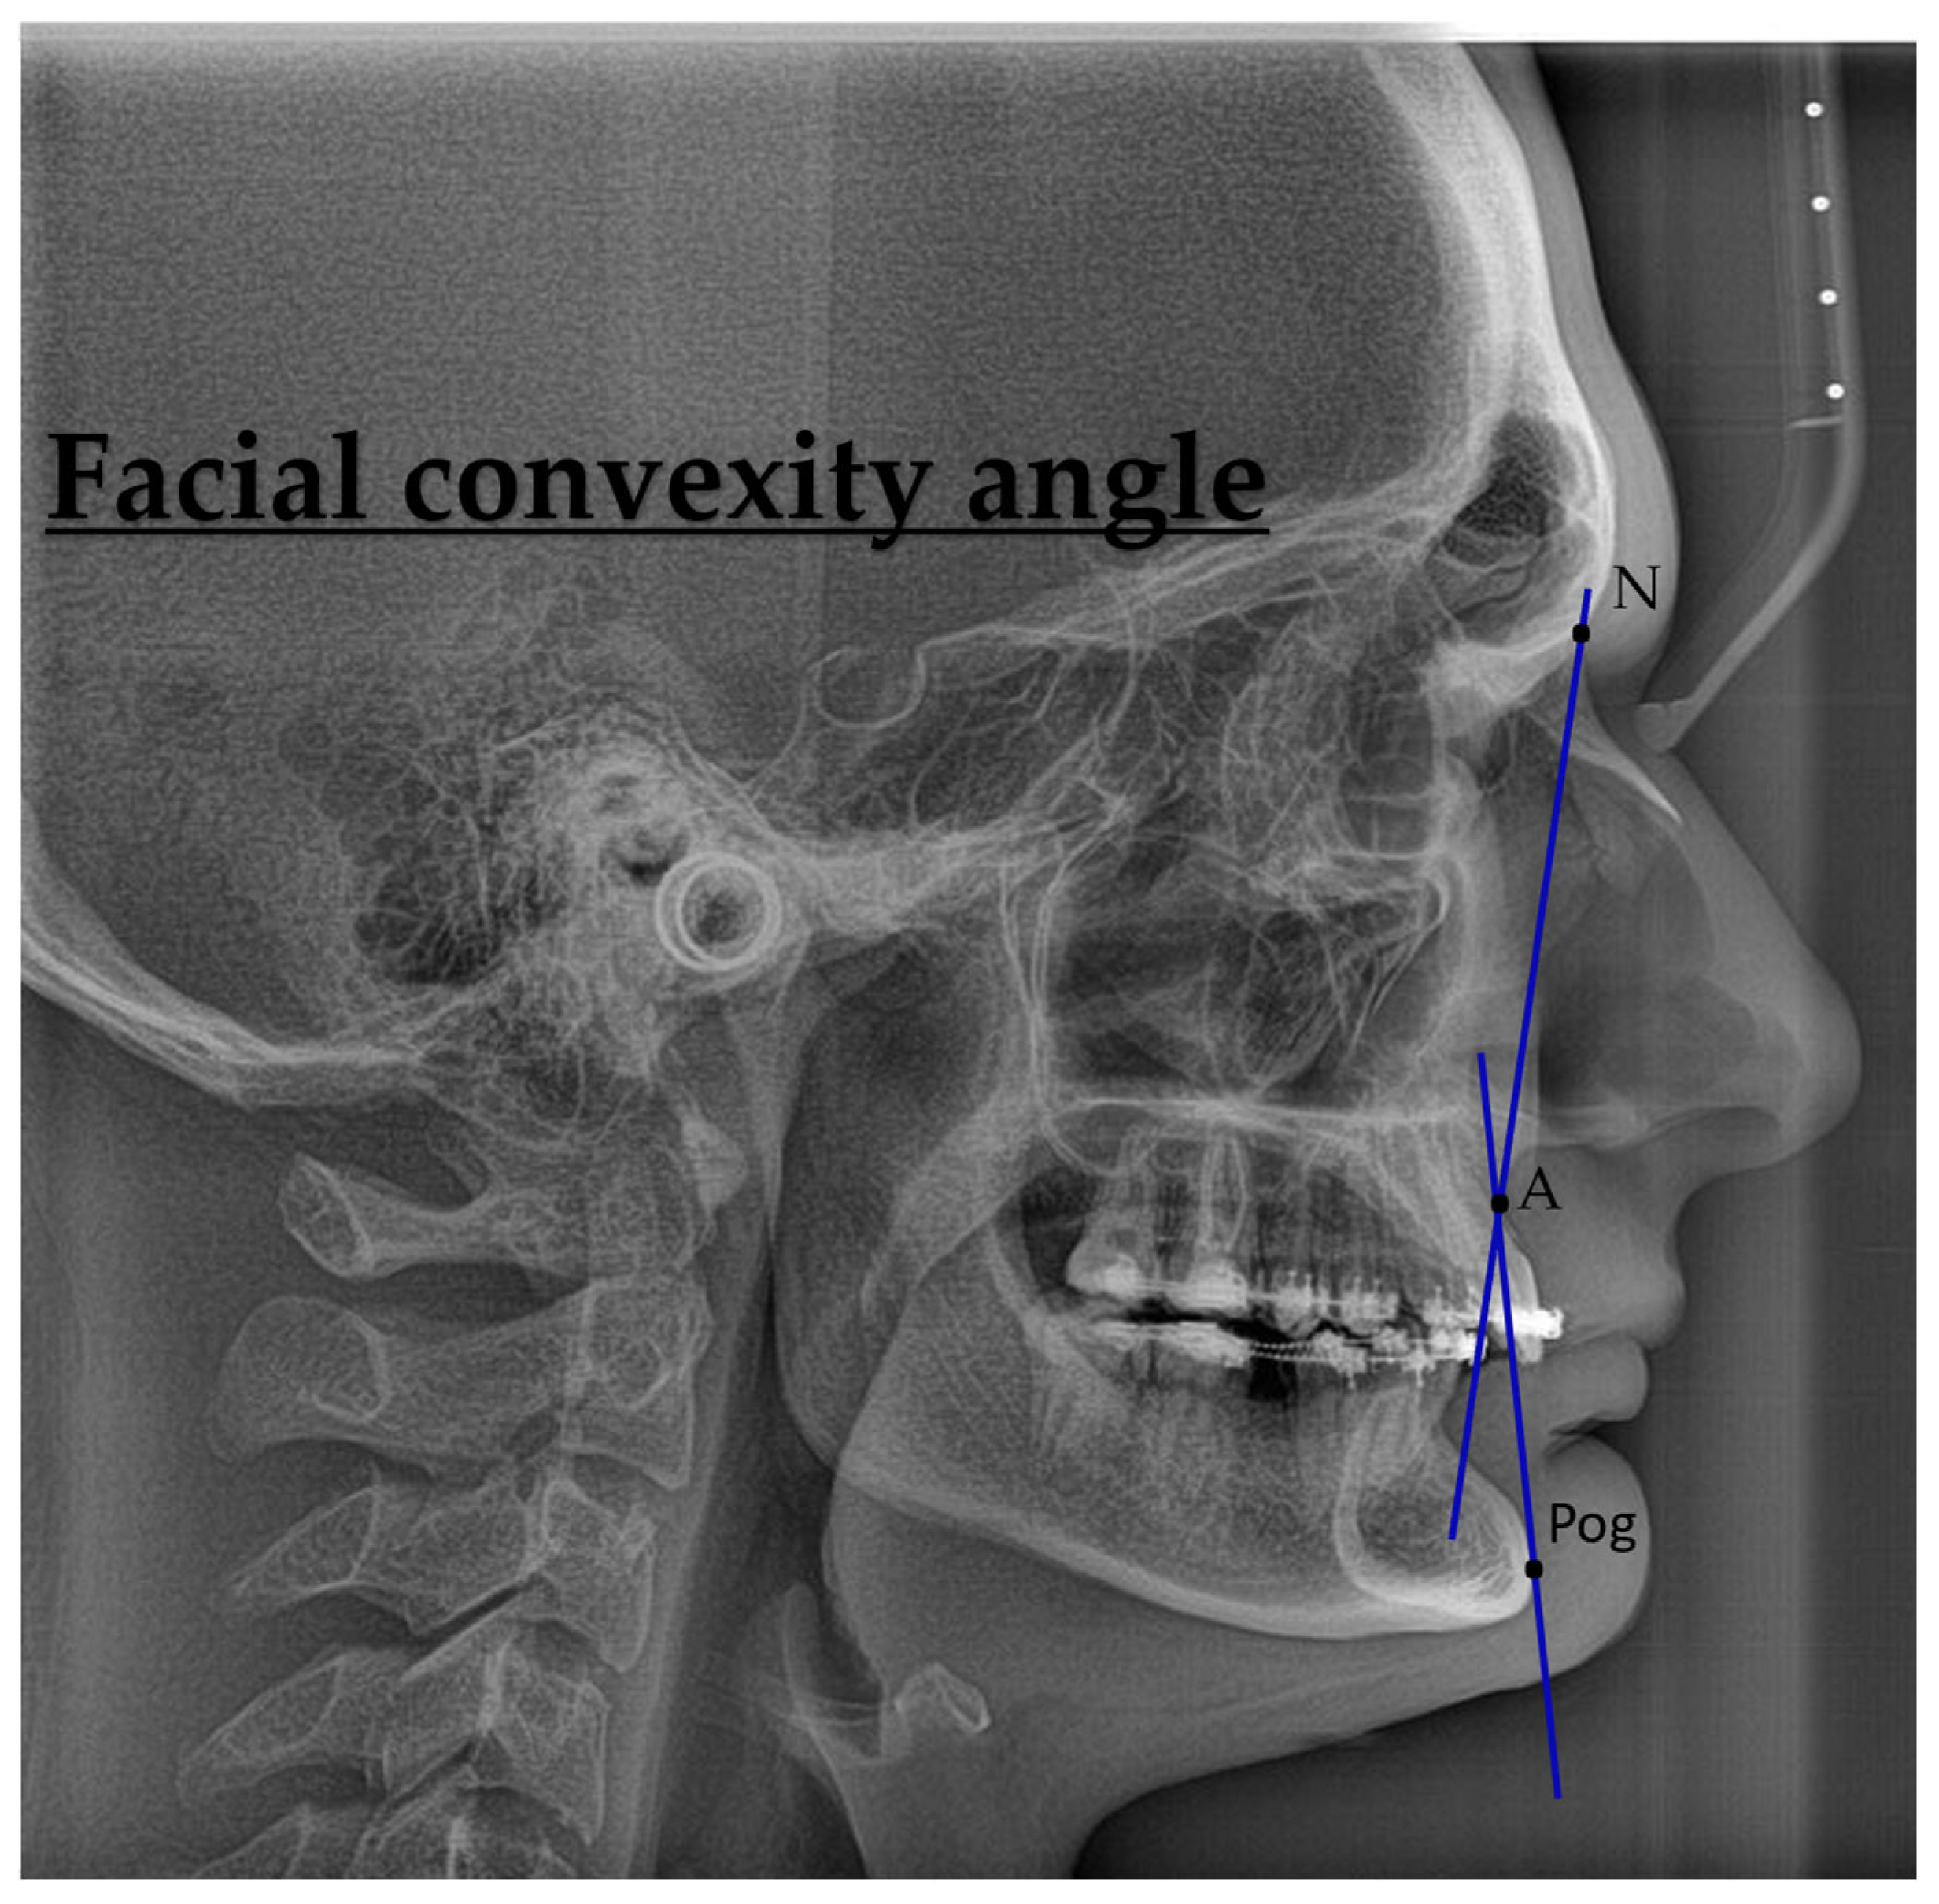

| Facial convexity (°) | 0 (−12, 7) | 2 (−6, 5) |

| Facial convexity (°) | −0.502 | 4.12 | −0.122 | 24 | 0.904 |